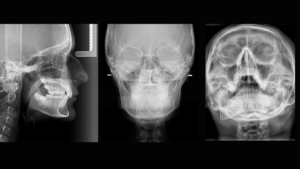

En nuestro Centro radiológico dental, contamos con equipamiento de vanguardia para ofrecerte los mejores resultados en radiografías dentales, radiografías panorámicas dentales, tomografía dental 3D y muchas más. Nuestro equipo de odontólogos está capacitado para brindarte la mejor atención para que tu dentista pueda tomar decisiones informadas sobre tu tratamiento. Además, nuestra radiología digital dental garantiza imágenes de alta calidad y reducción de daños por radiación. Si necesitas una radiografía panorámica dental, no dudes en visitarnos. Contáctanos para conocer nuestros precios y horarios de atención.